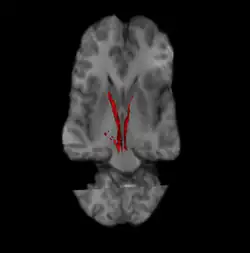

Nigrostriatal pathway (Left and Right in red).

The nigrostriatal pathway is a bilateral dopaminergic pathway in the brain that connects the substantia nigra pars compacta (SNc) in the midbrain with the dorsal striatum (i.e., the caudate nucleus and putamen) in the forebrain. It is one of the four major dopamine pathways in the brain, and is critical in the production of movement as part of a system called the basal ganglia motor loop. Dopaminergic neurons of this pathway release dopamine from axon terminals that synapse onto GABAergic medium spiny neurons (MSNs), also known as spiny projection neurons (SPNs),[1][2] located in the striatum.